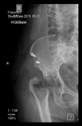

The radiological examination allowed us to verify the close bone-to-implant contact and the unchanged position of the implant during follow-up.

In all the cases operated with the above-described targeting procedure, the stems of the cups remained between the cortical bone surfaces without perforation of the linea terminalis, as shown by postoperative radiographs. There were no complicated surgical situations. In 16 cases, the wound healings were uneventful, and the hips were able to bear weight again after postoperative rehabilitation.